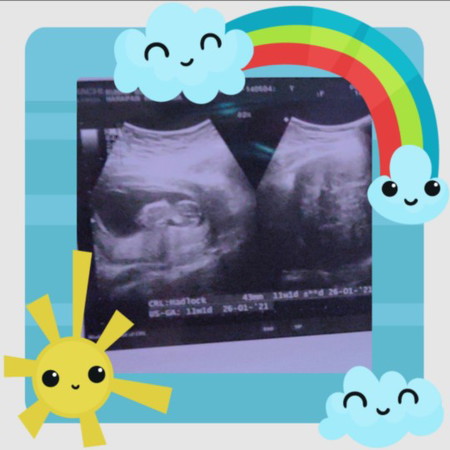

my baby

Ini Bun hasil USG kemarin?